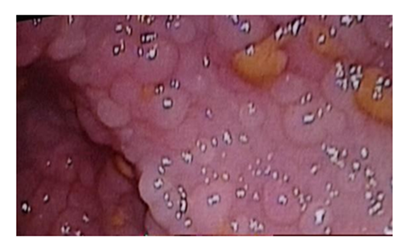

Familial adenomatous polyposis (FAP) is an autosomal dominant inherited condition, characterized by the development of hundreds to thousands of adenomatous polyps in the colon and rectum (Figure 1), caused by a mutation in the adenomatous polyposis gene (APC) occurring in 1 3:10,000 births, with almost 100% penetrance. In 20% to 30% of cases, the condition is caused by a spontaneous mutation with no clinical or genetic evidence of FAP in the parents or family. Hyer et al. [1] reported that the gene responsible for FAP, APC, is located on chromosome 5q21. Attard et al. [2] reported that FAP typically presents in childhood or adolescence, with the youngest reported case of polyps at age 7, with some patients requiring colectomy before age 10, especially those with APC gene mutations at codon 1309. Some studies reported that common symptoms include rectal bleeding, diarrhoea or constipation, abdominal pain, unexplained anaemia, weight loss (in more advanced stages) or completely asymptomatic identified through family screening [3,4]. Attard et al. [5] reported that upper gastrointestinal involvement is common, with fundic gland polyposis and duodenal adenomas frequently observed. Some ttudies showed that common extraintestinal manifestations include osteomas, congenital hypertrophy of the retinal pigment epithelium, and desmoid tumours [6,7]. It can also be presented as Gardner syndrome and Turcot syndrome. Gardner syndrome features extracolonic manifestations like osteomas and dental anomalies, while Turcot syndrome is associated with central nervous system tumours. Galiatsatos et al. [8] reported that these syndromes can occur simultaneously, suggesting they are phenotypic variants of FAP. Cazorla et al. [9] in a recent research identified new cancer types potentially associated with FAP, such as mucoepidermoid carcinoma of the parotid gland.